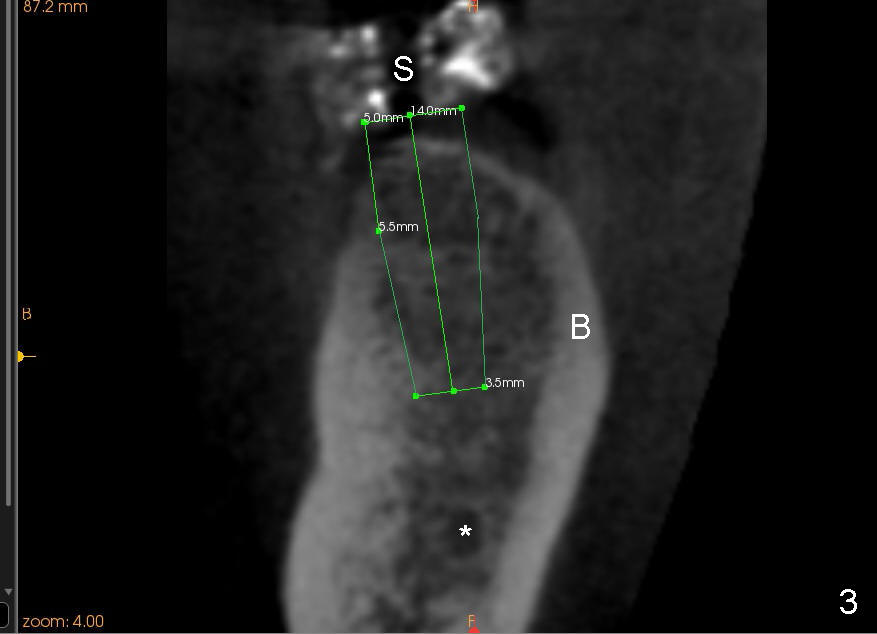

A 45-year-old man is a smoker (half pack a day). He returns for perio maintenance every 3 months. The teeth #18 and 19 have been extracted for long with supraeruption of #14 and 15 (Fig.1 arrows). CT confirms sufficient bone height (Fig.2) and width (Fig.3). Bone density is type II, as shown by CT and drilling. Relatively short implants are placed as deep as possible considering supraeruption of the opposing teeth (Fig.4 (4.5x14 and 5x14 mm taps at sites of #19 and 18, respectively) and Fig.5 (5x14 mm and 6x14 mm gingiva-level implants (I)). In order to avoid damaging the submandibular fossa, the implant at the site of #18 is tilted lingually (Fig.6). When short abutments (3 mm in height) are placed, there is enough clearance to place perio dressing. The abutment at the site of #18 becomes prematurely loose. It has to be removed 4 days postop. There is no sign of infection. Perio dressing is removed by the patient 7 days postop. He returns to clinic 8 days postop (Fig.7) for the remaining abutment to be removed. The wound appears to be healing normally.